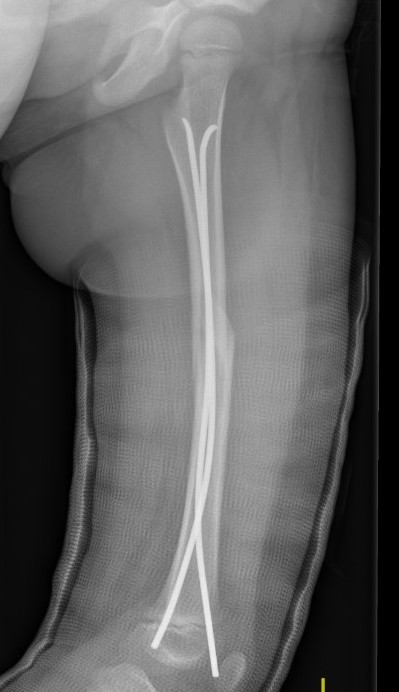

Flexible nails / Titantium Elastic Nails

Indications

Length stable fractures i.e simple transverse, short oblique

Midshaft fractures

Maximum weight up to 50 kg / 12 years old

Flexible nail technique

Wires

- available 1. 5 mm - 4.0 mm

- 30 - 40% of diameter of diaphyseal medullary canal

- i.e. if canal 10 mm wide, use 2 x 4 mm

- recommend using 2 wires same diameter to avoid rotational instability

Entry points

- medial and lateral insertion

- 1 - 2 cm proximal to distal femoral physis

- oblique entry with awl in direction of nail insertion

- can open with drill bit

- beware proximity of the femoral artery medially

- entry points should be symmetrical

Wire passage

- bend wire for 3 point fixation with bend at fracture site

- also bend the tip of the wire

- can use F Tool to reduce fracture / sheet in groin

- may need small incision and open reduction

- medial entry wire will pass into femoral neck

- lateral wire will pass into greater trochanter / medial wire into femoral neck

- use designated TEN wire cutter to cut wires

- cut off, tap in slightly further, leave 1.5 cm out so can retrieve

- wires that are too prominent can cause bursa / limit flexion / pain / protrude through skin